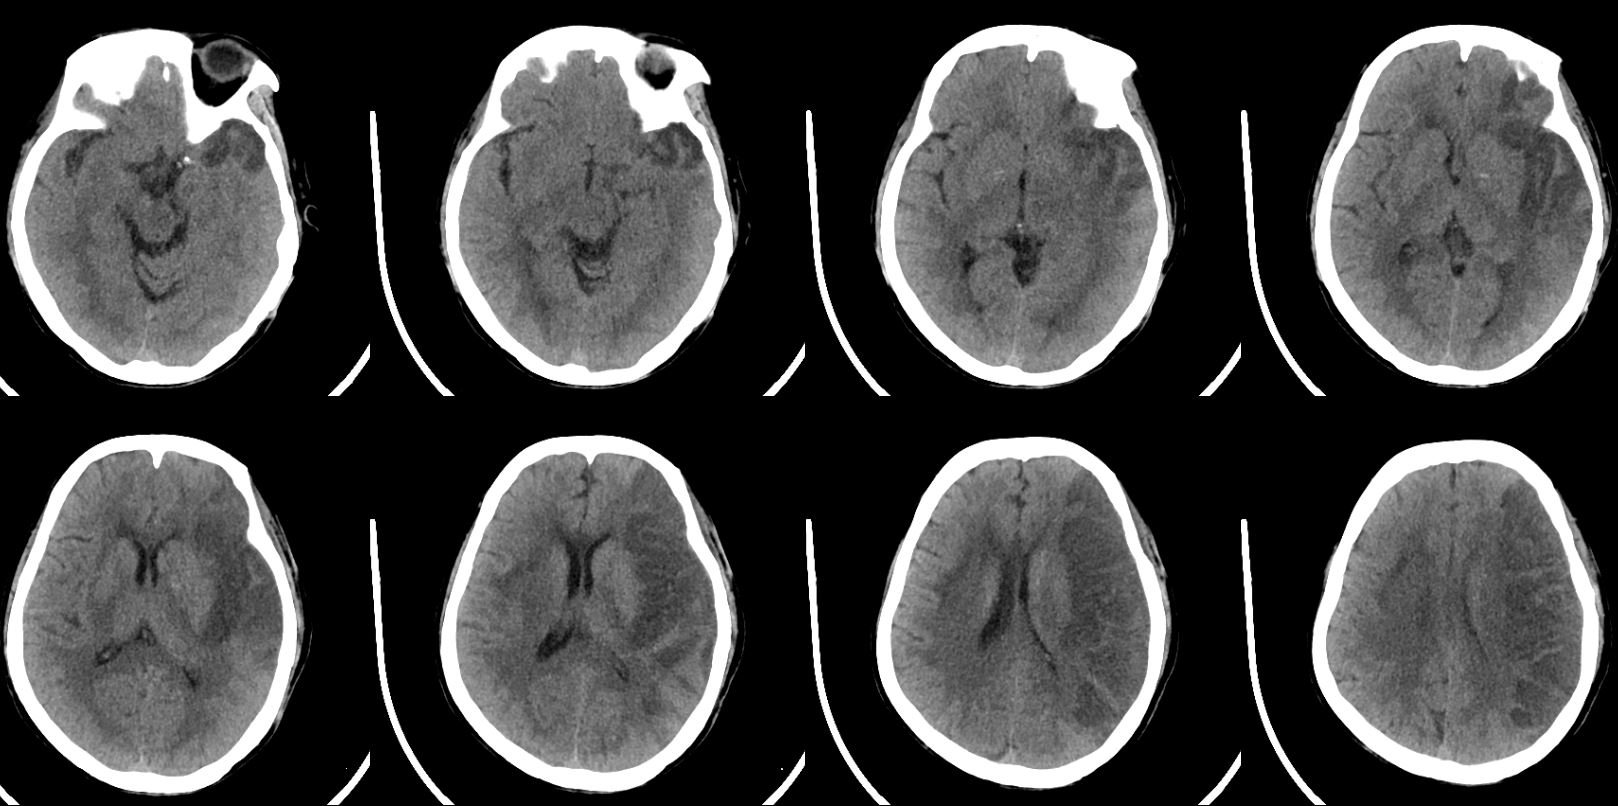

术后当天麻醉苏醒顺利,右侧肢体活动较术前好转,能抬离床面,考虑大面积脑梗死,术后予单抗、他汀、清除自由基等治疗。

复查CT无出血,无造影剂外渗,病灶范围较大,侧脑室受压,适当脱水,控制颅内压,考虑大面积梗死,又是ICAS,选择使用单抗。

此次复查患者颅内水中完全消退,片中所示低密度灶范围较术前明显减少,结合患者症状表现,患者明显获益。